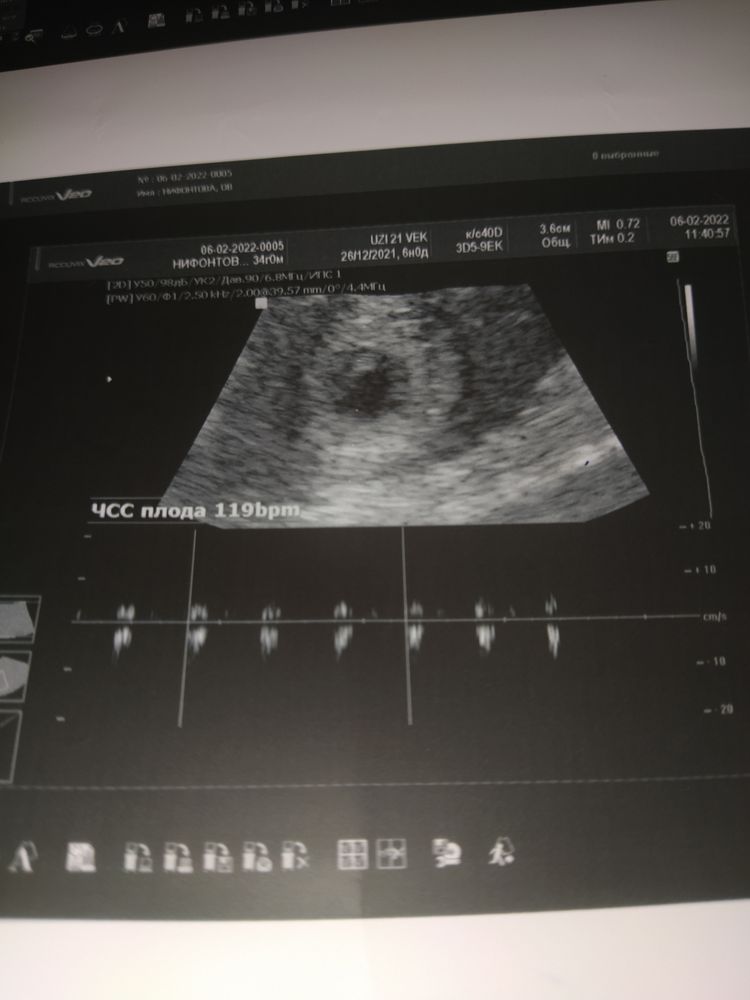

Узи 6 недель нет сердцебиения

Узи 6 недель нет сердцебиения 119 фотографий